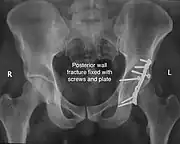

Posterior wall fracture fixed with screws and plate

| Posterior wall | This is the most common variety of acetabular fracture. It typically occurs due to dashboard injury; when a person travelling in a vehicle involved in a head-on collision, the force applied over the flexed knee travels along the femur bone to the head of the femur, breaking the posterior wall of the acetabulum. The head of the femur is dislocated outside the joint. | T shape | When a transverse fracture also had a vertical fracture line, it is called a T shape fracture. Here the innominate bone is broken in such a way that all three parts of it, the ilium, the ischium and the pubis are separated from one another. This is a three part fracture. Though both columns are broken, the weight bearing dome is still attached to the main part of the ilium and hence it is not a true fracture of both columns.